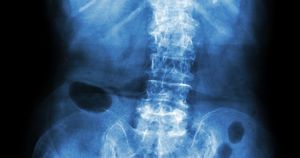

11. Widoczne na zdjęciu zwyrodnienie kręgosłupa to:

Obraz